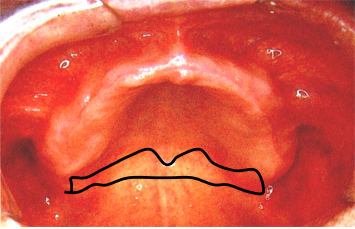

8.腭小凹(palatal fovea)

口内粘液腺导管的开口,位于上腭中缝后部的两侧。

上颌全口义齿的后缘应在腭小凹后2mm处 ,颤动线位于腭小凹的稍前部。

10.颤动线(vibrating line)

位于软腭与硬腭的交界部位。发“啊”音时软腭升高,发音结束后又复归原位,故又称“啊”线。

堵住鼻孔用鼻子出气会使软腭向下降,能明确观察到颤动线。

该线通常作为决定义齿基托后缘的标志,分前、后颤动线,两者之间为后堤区,宽约2~12mm 。

⑤后堤区: 腭小凹后方,轻压颤动线以获得良好的封闭。